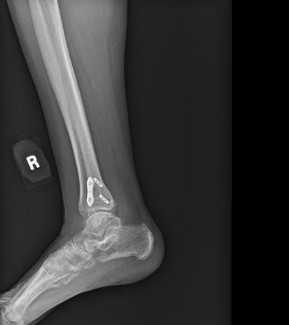

At his four-month follow-up, the patient was fully weight-bearing and had returned to work at full duty. He no longer required a brace and had full ankle stability with minimal pain. Follow-up X-rays showed complete healing with no hardware complications.